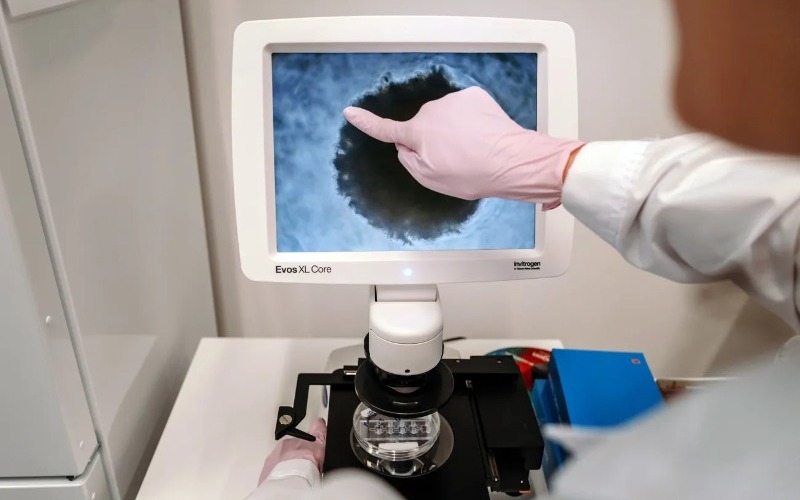

Un nuevo estudio del Centro Nacional de Investigaciones Oncológicas (CNIO) ha logrado identificar varios conjuntos de genes relacionados con...

Durante años, la metástasis cerebral ha permanecido en un segundo plano dentro de la investigación oncológica, a...

Un grupo de investigadores británicos anunció este miércoles un proyecto que analizará muestras antiguas de tumores de...